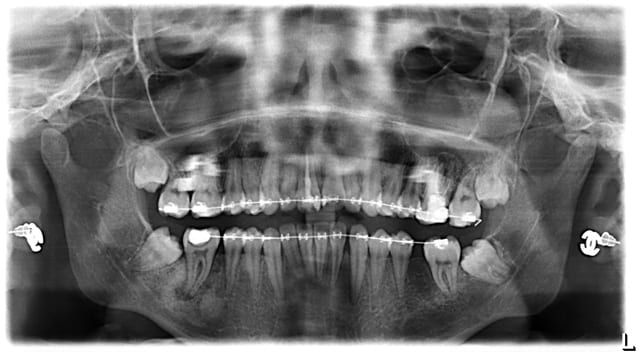

voici opour info les pano avant tt et en cours. la 36 a ete extraite et je m'imaginais que les 37 47 sortiraient seules...

Messafah s 19860715 70194472 6 fl9kqr - Eugenol

Messafah s 19860715 70162568 3 b5qan8 - Eugenol

Céramik, maintenant que tu as la pano, peux-tu nous dire où tu les mettrais tes "2 mini-vis pour 200 euros" ?

Au vu de la panoramique, il me semble que l'emplacement de choix soit la branche montante (vous voyez un autre emplacement ?).

Il y a deux problèmes cependant, la mobilité de la muqueuse si la vis émerge à cet endroit et la faible distance entre la tête de la vis et la ligature.

Il me semble que la 46 est manquante, et que c'est la 48 qui est incluse...

Il semble y avoir une lésion sous la 47...

oui désolé on parle bien des 8

Quand a la 47, elle est en cours de soin actuellement